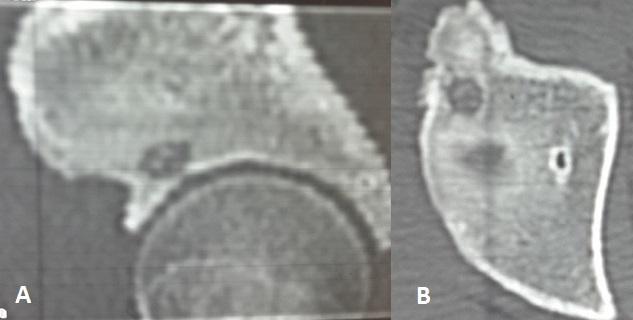

[Osteoid osteoma of the roof of the acetabulum: an exceptional location].

https://cdn.ncbi.nlm.nih.gov/pmc/blobs/b411/4546794/edc264c2755e/PAMJ-21-134-g001.jpg